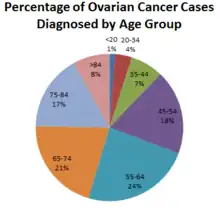

L'incidence est plus élevée en Europe et aux États-Unis, comparativement au Japon et aux pays peu industrialisés[1].

En 2005, et en France, l'incidence du cancer de l'ovaire a été de 8,1/100 000 femmes, avec une mortalité de 4,6/100 000 femmes. Les pics de l'incidence et de la mortalité par tranche d'âge se situent entre 55 et 94 ans. Avec une incidence de 4,375 nouveaux cas diagnostiqués en France en 2005 il représente 3,2 % de l’ensemble des nouveaux cancers féminins. Avec 3,180 décès par an, le cancer de l’ovaire se situe au 13e rang de l’ensemble des décès par cancer, et au 4e rang des décès par cancer chez la femme[2],[3].